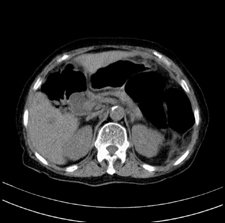

患者,女,75岁。腹痛,体黄5日,膝胸位时腹痛缓解。肝功能明日出来。彩超提示胆总管占位,未见血流信号。心电图提示s-t段改变。患者体质较弱,未能增强。

胆总管多发结石伴肝内外胆管轻度扩张。

胆总管上段,腔内有软组织密度影 ,ct值36-44hu。大家看有没有胆管癌的可能。

典型胆总管多发结石;增强扫描前后ct值是否发生改变是鉴别结石与占位的依据。